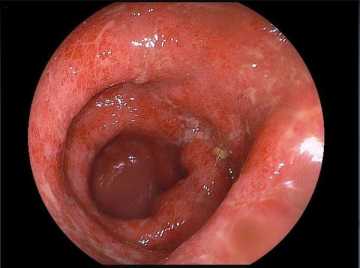

- колоноскопию с биопсией;

Преимущественно поражается прямая и сигмовидная кишка, заболевание протекает по типу колита. Пациента беспокоит частый жидкий кашицеобразный стул скудного объёма с обильными примесями слизи и крови (стул по типу “малинового желе”), наличие тенезм (болезненные и ложные позывы на дефекацию), а также императивные (неотложные) позывы на дефекацию. Характерно наличие болей в животе, чаще в нижней половине с левой стороны или болезненность в области заднего прохода.